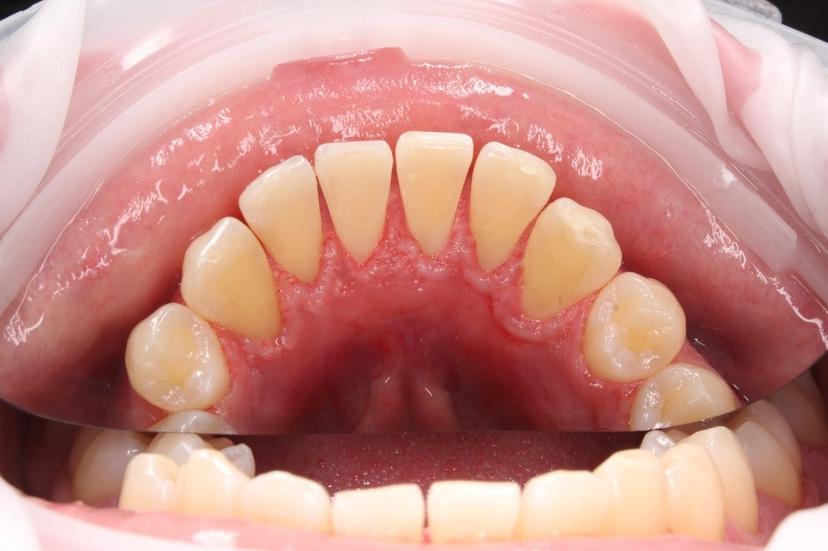

Обработка зубов системой AirFlow для снятия пигментированного, мягкого налета всей группы зубов

Обработка всей поверхности зубов системой AirFlow, снятие пигментированного зубного налета

Профессиональная гигиена полости рта системой AirFlow для снятия пигментированного налета; ультразвуковым скейлингом для снятия твердого зубного налета (зубной камень)

Профессиональная гигиена полости рта с использованием системы AirFlow для снятия пигментированного налета, а так же ультразвуковым скейлингом для снятия твердых зубных отложений (зубной камень)